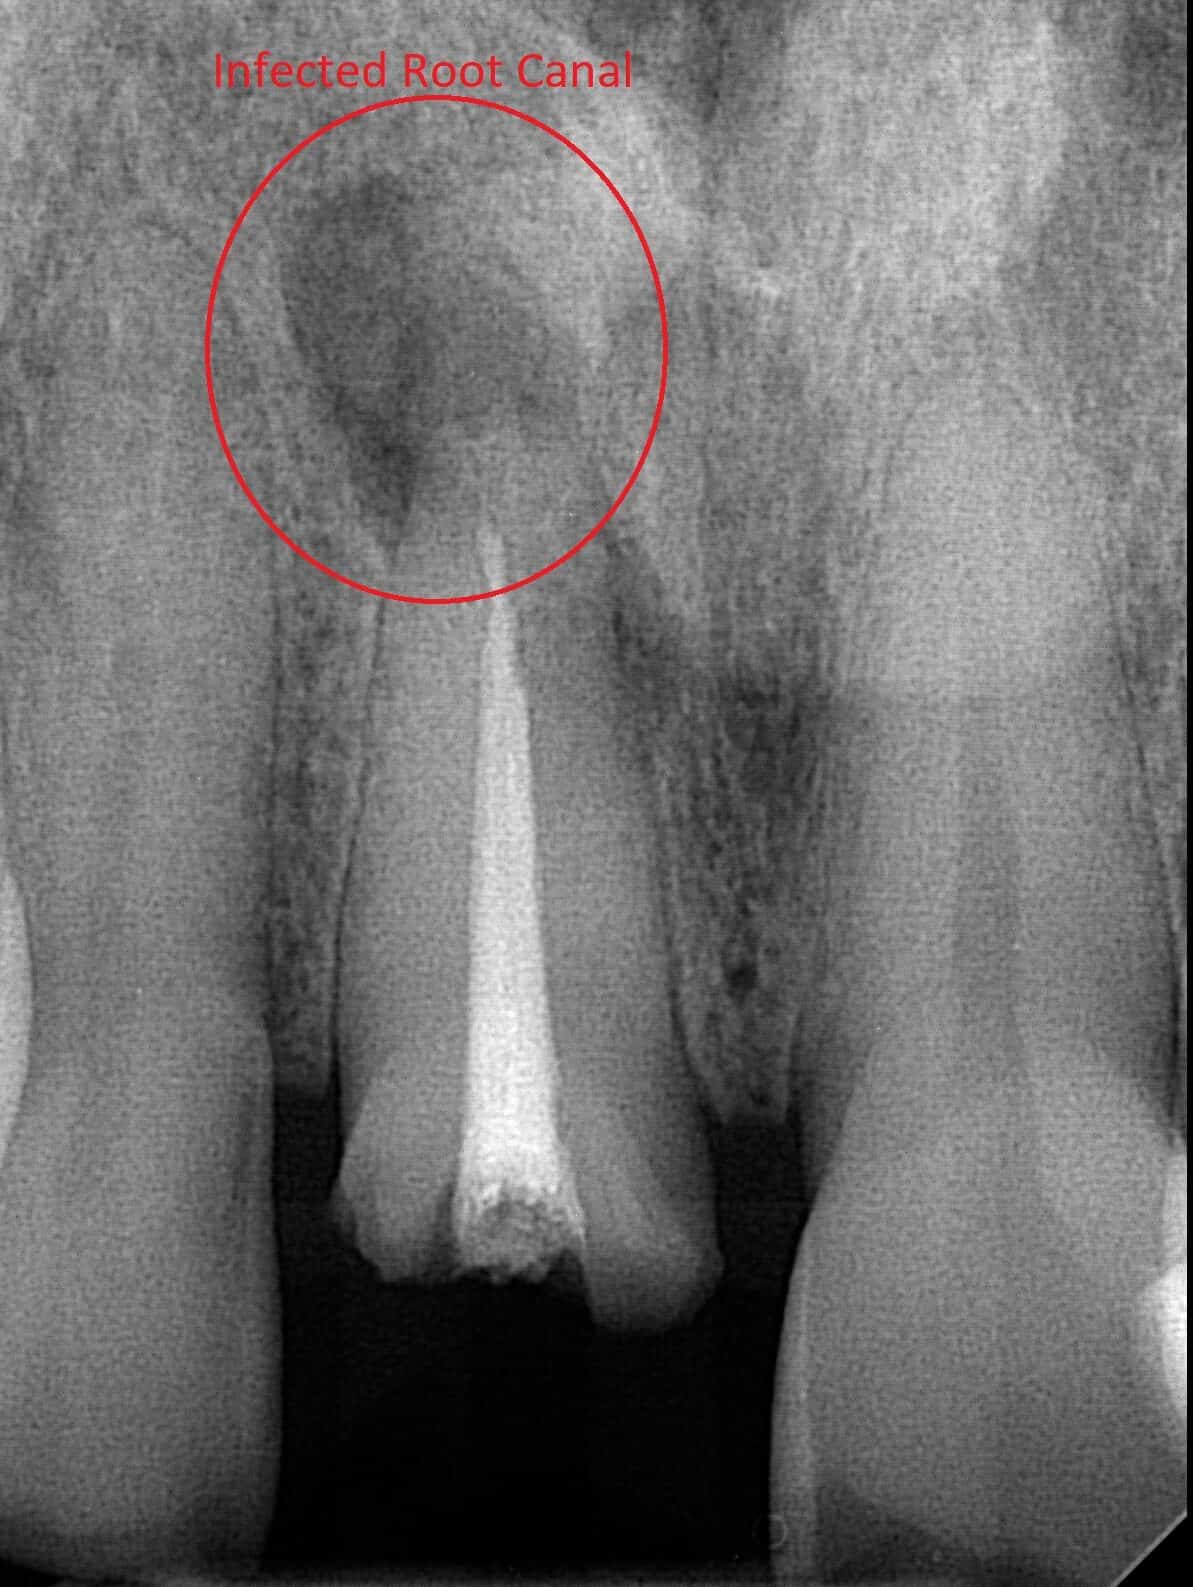

A 54 year old male patient came in for a dental emergency because his front tooth broke. An x-ray also revealed a large infection at the apex of the tooth.

To Fix this tooth we first need to remove the infection. A root canal re-treat was performed by a root canal specialist (Endodontist)